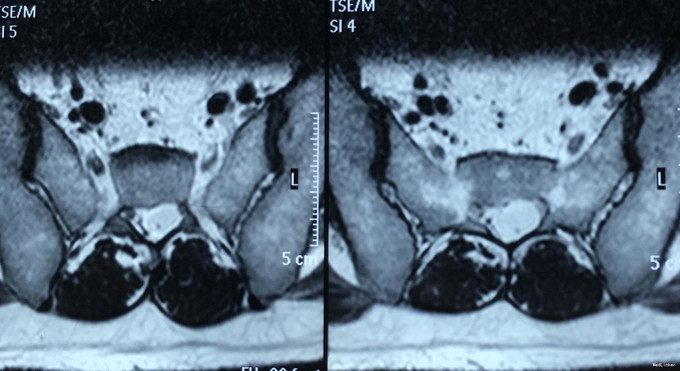

查体:脊柱生理弯曲存在,腰椎活动受限,L4/L5,L5/S1棘突压痛叩痛,叩击痛。左侧直腿抬高试验(+),约35°,加强试验(+),约30°。左下肢外侧皮肤感觉稍减退,右侧正常。双侧髂腰肌、股四头肌肌力Ⅴ级、左侧胫前肌、踇背伸肌肌力Ⅳ级,腹壁反射、肛门反射正常,两侧膝正常,双侧踝反射对称减弱。双侧Babinski征(-),双侧皮温及色泽正常,双侧足背动脉搏动良好。 辅助检查:腰椎磁共振检查显示:腰4/5椎间盘向左后方突出,压迫左侧神经根。骶管骶4水平发现一大小约2*3*3大小的囊肿。

诊断:1.腰4/5椎间盘突出症;2.骶管囊肿; 治疗:给予行左侧腰4/5椎板间开窗髓核摘除术。术后左腰臀部疼痛缓解明显,瞩其定期复查腰椎核磁共振。